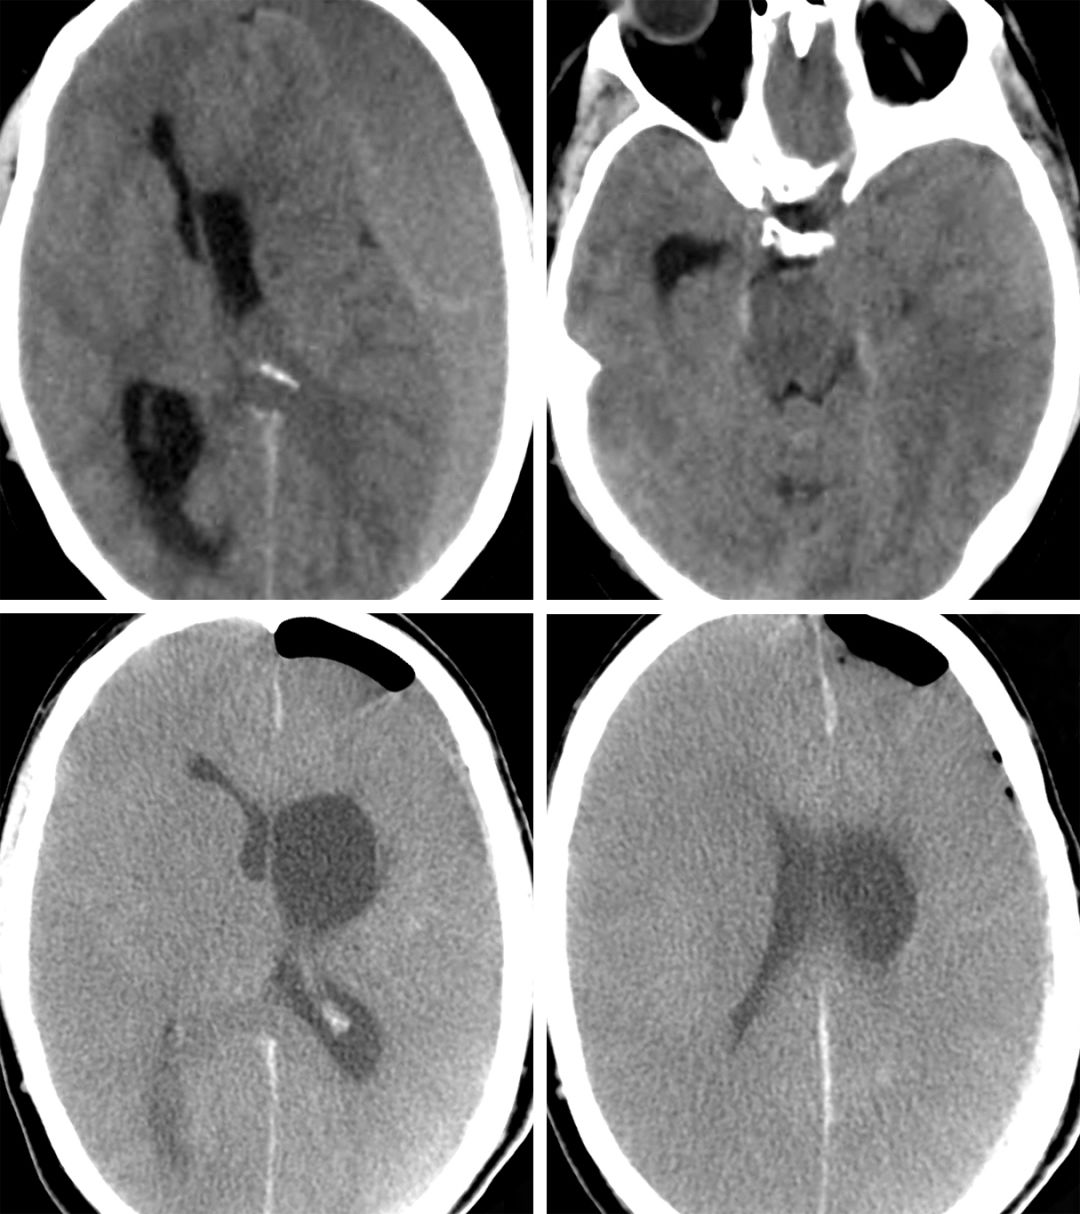

非增强CT不仅用于识别cSDH的存在,也用于明确血肿形成时间,这对选择术式有意义重大。与正常脑组织相比,aSDH表现为高密度,sSDH表现为等密度,而cSDH则表现为低密度。这种密度上的差别是由于血肿成分随时间演变而造成的。血肿通常包含一种主要成分,但同时伴有多种其他成分。

随着时间的推移,血肿的液体含量逐渐增多,导致其在CT上表现为低密度。这种血液粘度的变化也使得外科干预措施有所变化。确诊一般无需加做增强CT,但是,对于等密度的亚急性硬膜下血肿,增强CT可准确显示血肿边界。

图1. 图示左侧额叶sSDH的CT影像,病变呈等密度。红色箭头标注了血肿的边界。由于其与大脑正常组织密度相仿,因此较难判断。另外,此CT展示了SDH的占位效应导致的中线偏移。

图2. 图示一慢性、亚急性混杂SDH。请注意位于后方的亚急性血肿。

图3. 左图示急性SDH(高密度区),右图示慢性SDH(低密度区)。请注意慢性SDH所形成的腔隙间隔,这使得钻孔完全引流血肿的难度增大。